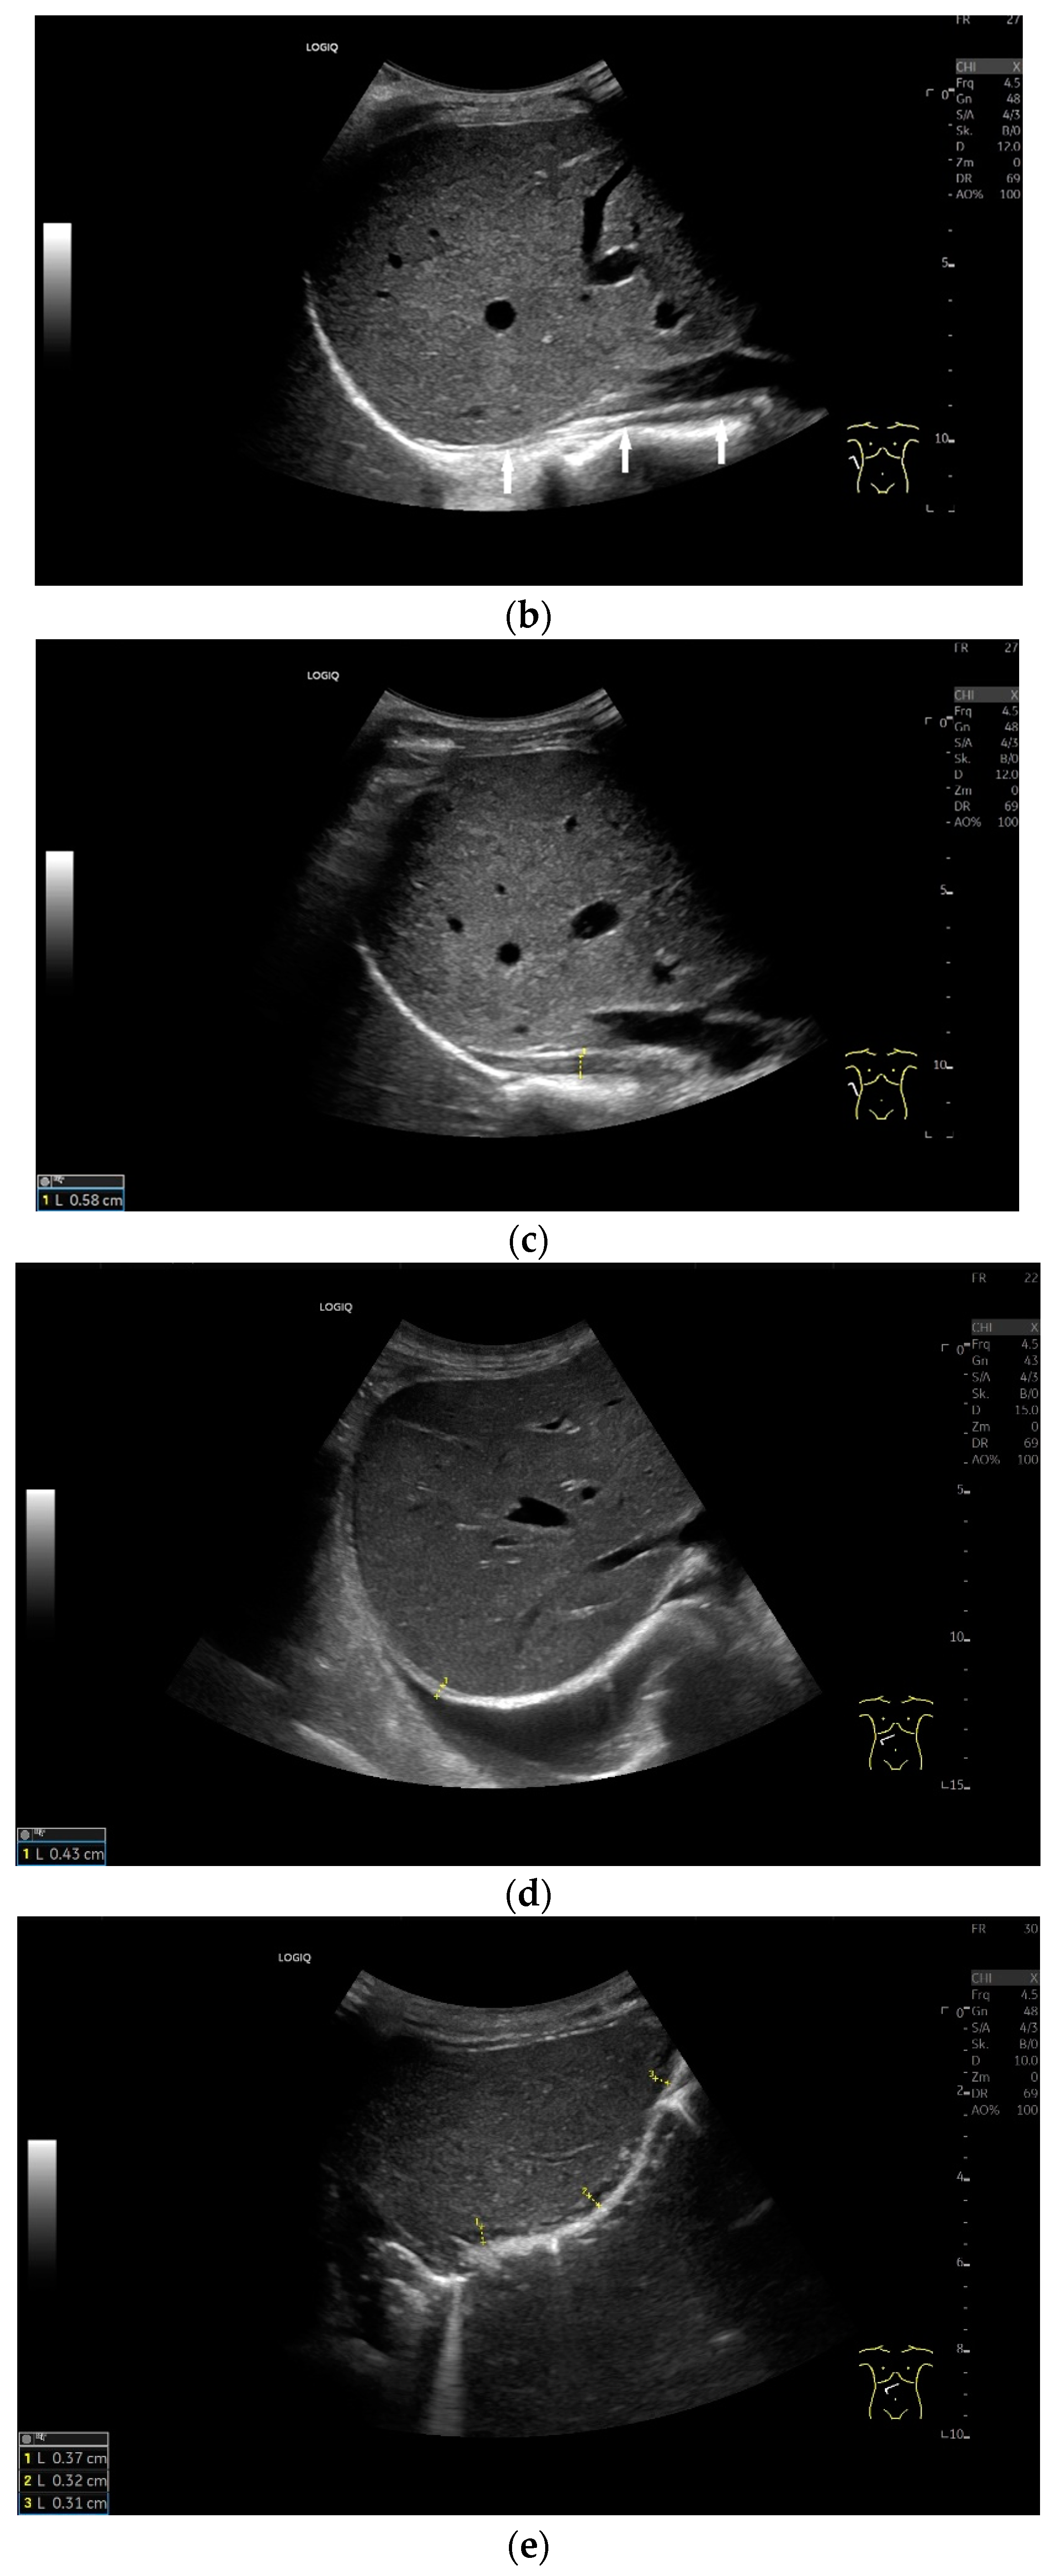

Subcostal transducer position: An abdominal sector or cardiac transducer (2–5 MHz) is used in the subcostal window. This position is used to assess diaphragmatic excursion. The transducer is placed between the linea medioclavicularis and linea axillaris anterior. The diaphragmatic excursion can then be visualized and measured in M-mode (Figure 5). The gallbladder and inferior vena cava are important landmarks. It is important to guide the ultrasound probe as perpendicularly as possible. The M-mode axis should meet the diaphragm at an angle of 90%. In this position, diaphragm thickness in inspiration and expiration can also be measured using M-mode, and diaphragm shortening can be calculated. However, in normal adults, the diaphragm can usually only be visualized in this position using abdominal sector transducers and is less accurately delineated than with a linear transducer from the lateral side in the anterior axillary line.

Diaphragmatic excursion and amplitude reflect the range of mobility and contraction. They can be assessed using different breathing maneuvers: during quiet breathing, with deep inspiration and during sniffing. A sniff maneuver is a short, forced inspiration. The movement of the diaphragm is ideally mapped in M-mode. The amplitude of diaphragmatic movement can then be measured on the M-mode curve, as can the speed of the diaphragm excursion. Standard values in numerous studies for diaphragm thickness, contraction and movement amplitude depending on body position, gender and diaphragm side are listed in Table 1 and Table 2. In addition to mean values and standard deviations, various studies also report the lower limit of normality of diaphragm thickness and contraction as well as the derived parameters. These are limit values that indicate how high a parameter must be in order not to be considered pathological. In this way, patients with dysfunction can be identified. There is also information on the upper limit of normality. However, the meaning of such a value is not entirely clear.